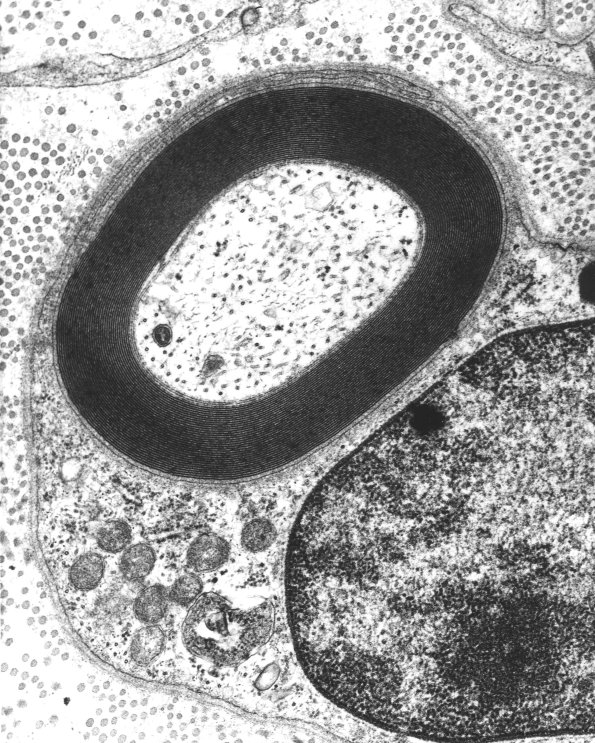

A normal appearing small myelinated axon is seen at two magnifications. (electron micrographs)